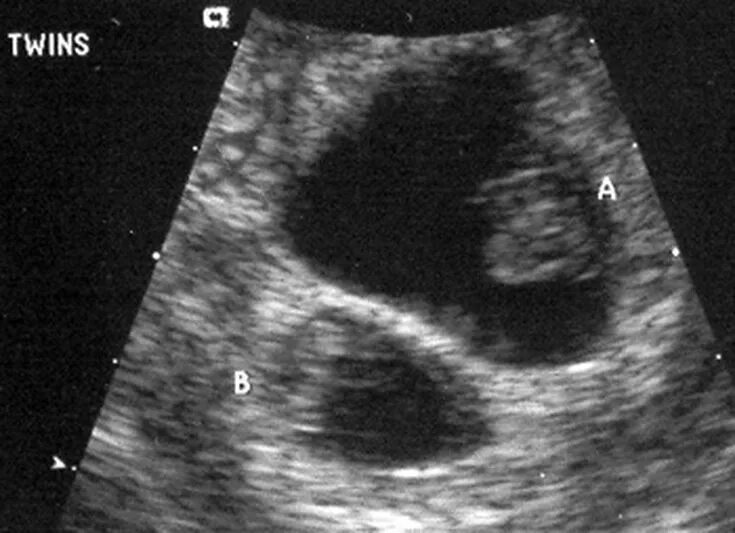

На каком сроке можно увидеть двойню